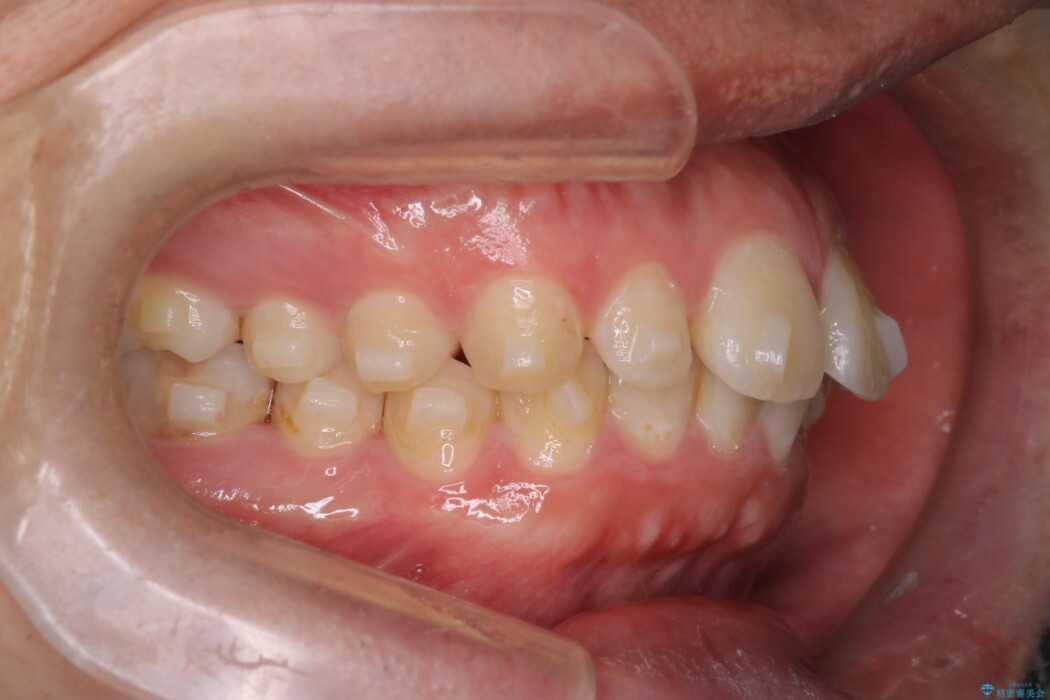

前歯中央の隙間と前に歯が出ていることを改善したいと来院されました。

正中離開(上の前歯中央の間に隙間があいている状態)は左右の歯を寄せることで隙間をなくし、IPRを用いてスペースを確保しつつインビザラインにて並べることとしました。

主訴である前歯中央の隙間は埋まり、前突も下げることができました。また審美的にもきれいな歯並びに仕上がって患者様にご満足いただけました。

舌側に倒れこんでいた奥歯の傾きも矯正したことにより正常角度になり、噛み合わせも改善しています。